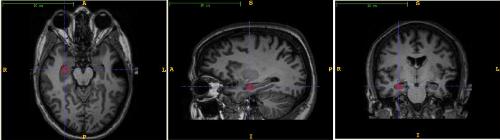

En un estudio realizado por Rasmussen et al. (2015) se compararon personas sanas y personas con el síndrome de Cushing. Se observó que existía una alteración en la sustancia gris del cerebro. Aspecto que revelaría la atrofia cerebral en los pacientes diagnosticados, como el déficit en la velocidad de procesamiento y la cognición. Resultados que exponen el grave deterioro en quienes presentan dicha condición.